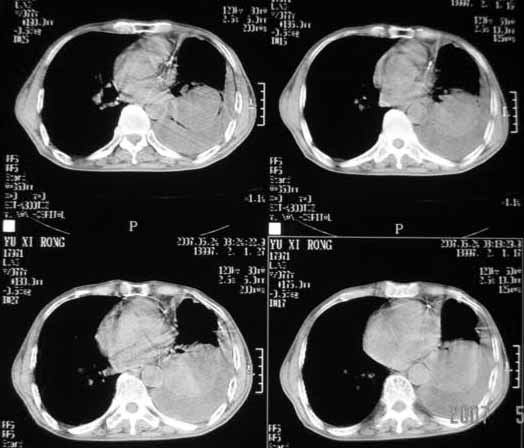

以下是引用luochengyi在2007-5-24 14:33:00的发言:[br]考虑左下肺癌。左侧胸腔积液。

以下是引用adams在2007-5-24 17:12:00的发言:[br]支持“考虑左下肺癌,左侧胸腔积液,建议胸水检查”。[br] [br]

以下是引用fumaogui在2007-5-24 16:20:00的发言:[br]左侧胸腔积液.[br]左下叶不张考虑中心型肺癌[br]建议纤支镜检查.